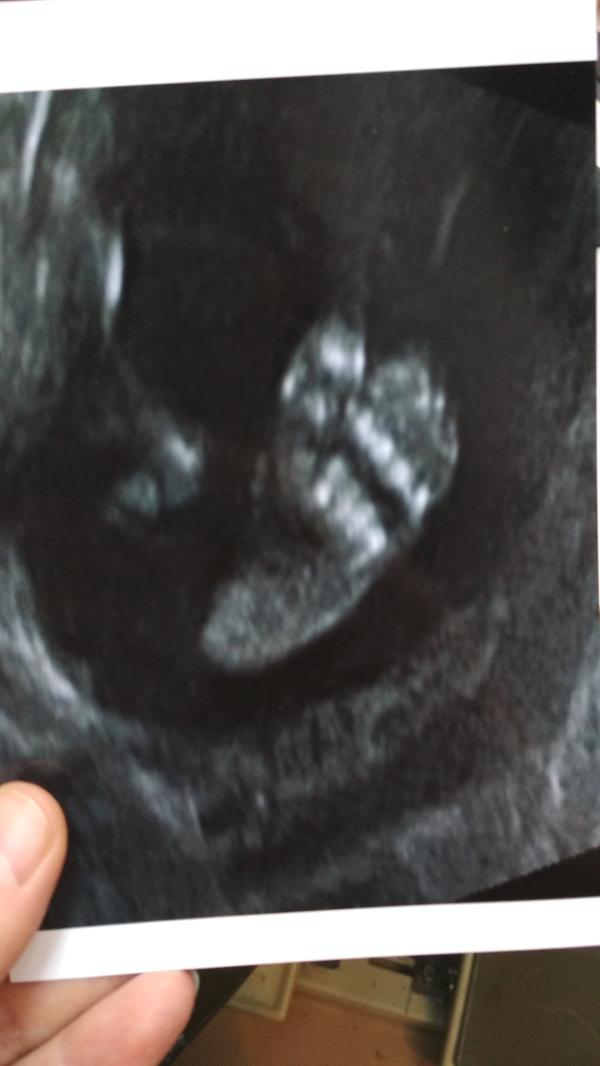

Второй скрининг пройден, наша долгожданная дочурка: эмоции и впечатления будущей мамы

Вот и у нас прошёл второй скрининг.

Моя долгожданная пуговичка 🥰

Уже всем сердцем любимая дочурка.